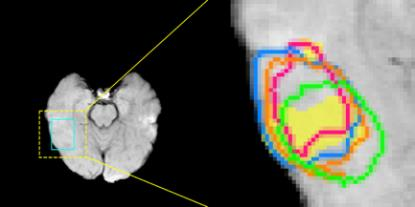

Accurate magnetic resonance imaging (MRI) segmentation is crucial for clinical decision-making, but remains labor-intensive when performed manually. Convolutional neural network (CNN)-based methods can be accurate and efficient, but often generalize poorly to MRI's variable contrast, intensity inhomogeneity, and protocols. Although the transformer-based Segment Anything Model (SAM) has demonstrated remarkable generalizability in natural images, existing adaptations often treat MRI as another imaging modality, overlooking these modality-specific challenges. We present SAMRI, an MRI-specialized SAM trained and validated on 1.1 million labeled MR slices spanning whole-body organs and pathologies. We demonstrate that SAM can be effectively adapted to MRI by simply fine-tuning its mask decoder using a two-stage strategy, reducing training time by 94% and trainable parameters by 96% versus full-model retraining. Across diverse MRI segmentation tasks, SAMRI achieves a mean Dice of 0.87, delivering state-of-the-art accuracy across anatomical regions and robust generalization on unseen structures, particularly small and clinically important structures.